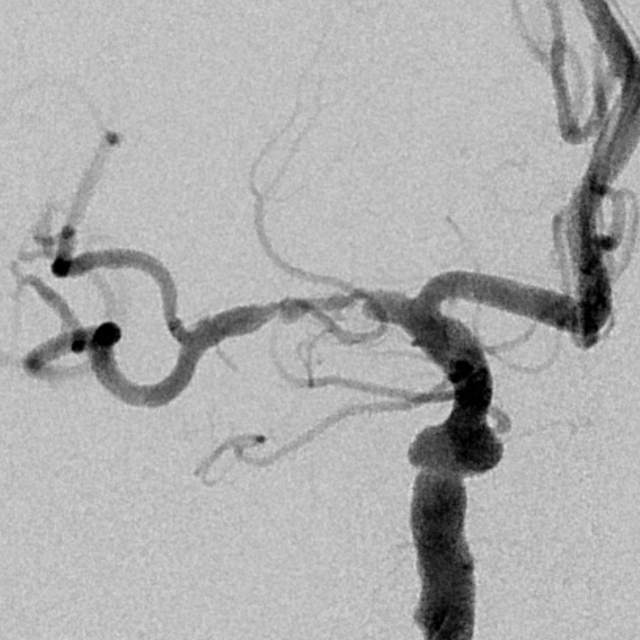

78岁老年男性,最近一个半月来已经和家里人没法正常交流,认知能力大幅下降,在农村,可能也就认为年龄大了,听天由命了。可老人家就是福大命大,有亲戚做医生,间隔17天先后为老人做了两次头颅MRI,发现脑梗塞,右侧血管长节段严重狭窄,右侧大脑半球缺血严重(图6,满江红),手术风险大……,家属经过反复咨询、犹豫、权衡,选择了保守治疗,毕竟老人年龄大了,手腿现在还能动,手术也有风险,时机也不是太好,国外研究不推荐,国内研究也不支持,保守治疗似乎是个不错的选择。然而,保守期间,患者反复出现脑梗塞,认知能力进行性下降,最终促使家属决定采用外科干预。然而,对医生而言,在梗塞的急性期处理这种长节段密布分支血管的病变风险不言而喻,而一味的观望和等候肯定不是最佳选择。过一点,可能出血;欠一点,可能闭塞。全面认真评估后,我们顺利为老人家完成了I期治疗,老人家的“火焰山”(图6)变成了“绿油油”充满生机的田野(图14),缺血明显改善,认知能力大幅提高,术后就能和家人正常交流了,也记起了很多以前忘记的事情……,家人很开心。